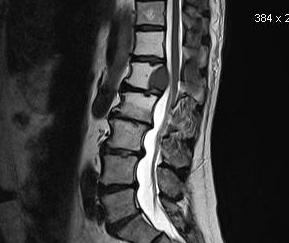

STIR

A method for fat suppression

- very important for TI and gadolinium

- changing the appearance of fat from white to black

- important for T2 to highlight fluid